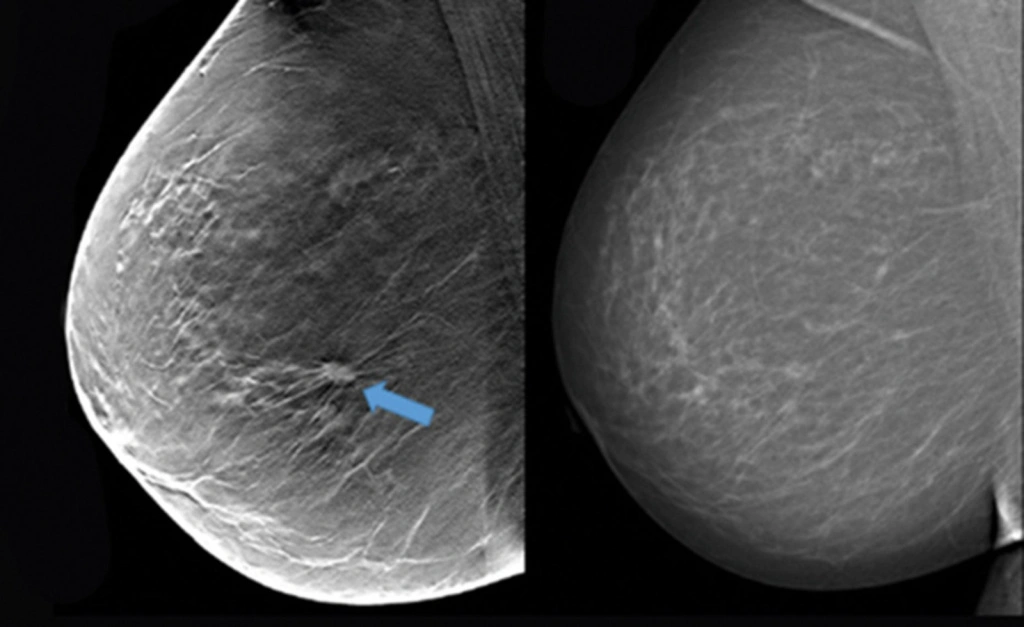

Женщины знают, что в течение жизни необходимо следить за состоянием своей груди, проводя самообследование и посещая врача, чтобы вовремя обнаружить проблемы, требующие лечения. Одним из исследований, необходимых для проверки тканей груди, является маммография.

Ростовчан и гостей города клиника «ДонМед» приглашает на обследование, которое проводят на современном оборудовании экспертного класса. Его выполняет специалист с большим опытом работы, который может обнаружить даже незначительную патологию.

После обследования специалисты клиники «ДонМед» в кратчайшие сроки подготовят расшифровку маммографии молочных желез, что позволит в случае необходимости сразу же приступить к лечению и не допустить развития осложнений. Не откладывайте на потом, пройдите обследование уже сейчас, чтобы быть уверенными в собственном здоровье.